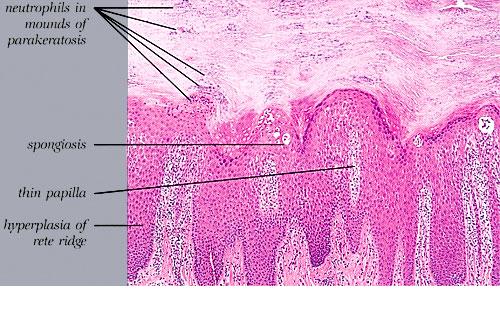

In pustulosis palmaris et plantaris there is a fully developed large intraepidermal unilocular pustule. It is elevated only sligtly above the surface but presses onto the underlying dermis. Many neutrophils are present within the cavity of the pustule. The epidermis surrounding the pustule shows slight acanthosis, and an inflammatory infiltrate can be seen beneath the pustule . In many instances one can observe typical, although small, spongiform pustules in the epidermal wall of |

the ustule, most commonly at the junction of the lateral walls and the overlying epidermis . These spongiform pustules are identical to those seen in the walls of the pustules of generalized pustular psoriasis. |

Very early lesions may show spongiosis and exocytosis of lymphocytes in the lower epidermis overlying the tips of dermal papillae (. This may be followed by the formation of a small intraepidermal vesicle containing mostly lymphocytes . Subsequently, there is a massive exocytosis of neutrophils, which penetrate the intercellular spaces of the vesicle wall, where the histologic picture of spongiform pustules is then seen . In the acute form, pustular bacterid, leukocytoclastic vasculitis has been described . |